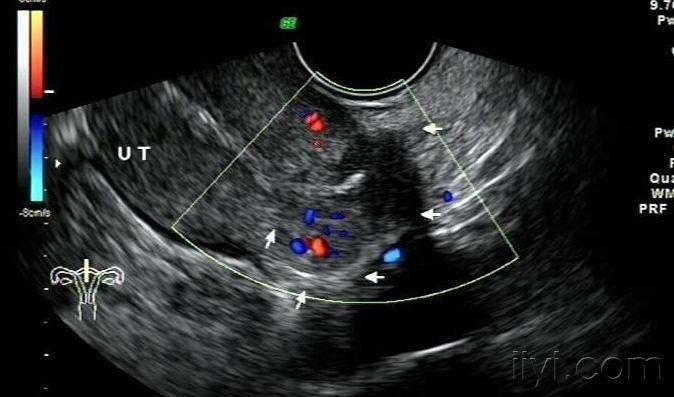

子宫穿孔的超声诊断

超声诊断子宫穿孔并大网膜嵌顿1例

超声典型病例子宫穿孔

子宫穿孔彩超下表现

子宫穿孔超声表现图